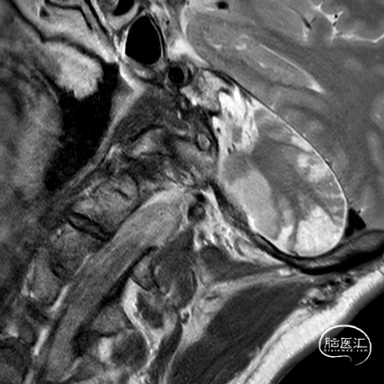

现病史:患者今年2月份出现头晕伴左侧肢体无力,MR诊断为脑干及双侧小脑梗死,治疗后好转。一直口服阿司匹林+波立维治疗;4月份患者出现视物成双伴口角歪斜,MR诊断为右侧小脑及左侧丘脑梗死。

2024年4月17日

拟尝试行椎动脉再通术

进一步经右侧桡动脉造影明确右侧椎动脉病变

莫非是变异+夹层?